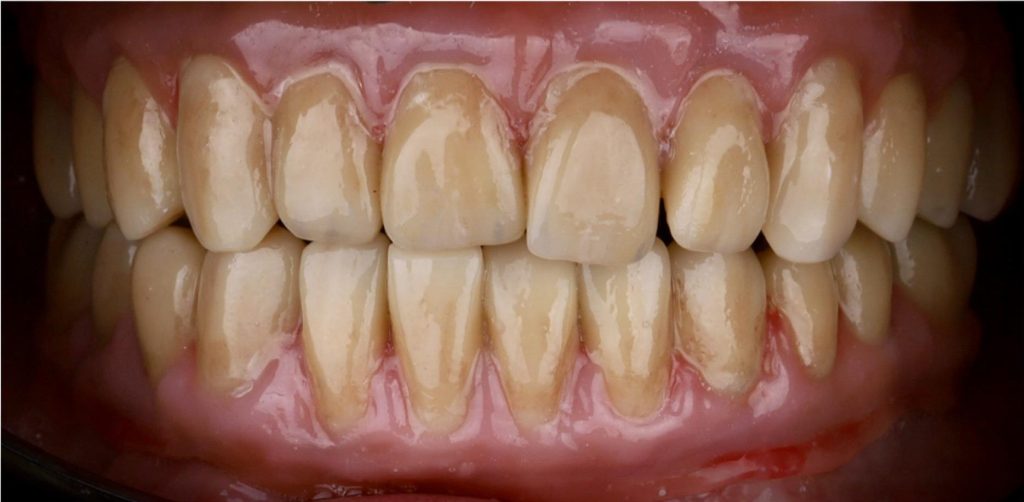

Przeprowadziliśmy precyzyjne leczenie implantologiczne, wszczepiając 11 implantów w szczęce i żuchwie. Konieczna była też regeneracja kości. Po 6 miesiącach gojenia nastąpiła odbudowa pełnołukowa. Kształt, kolor i ustawienie zębów zostały dobrane oraz wykonane na indywidualne życzenie Pacjenta.

Leczenie chirurgiczne i implanto-protetyczne przeprowadził lek.stom. Michał Badowski.